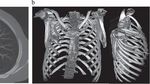

Saat itu, dokter berhasil menutup luka-lukanya dengan jahitan, dan sejak itu ia menjalani kehidupan yang relatif normal, hingga putingnya mulai mengeluarkan nanah. Karena penyebab infeksi tidak jelas, dokter memutuskan melakukan pemeriksaan rontgen. Hasilnya, ada sebuah bilah pisau berukuran besar ternyata tertancap di dalam dada pria tersebut. (Foto: Journal of Surgical Case Reports).

“Pencitraan awal dengan radiografi dada lateral menunjukkan adanya benda logam yang tertahan di bagian tengah toraks, dengan kekeruhan di sekitarnya yang kemungkinan merupakan hematoma terlokalisasi kronis atau yang sudah sembuh, atau fibrosis pascatrauma, yang merupakan sekuel dari luka tusuk pasien,” tulis para dokter. (Foto: Journal of Surgical Case Reports).